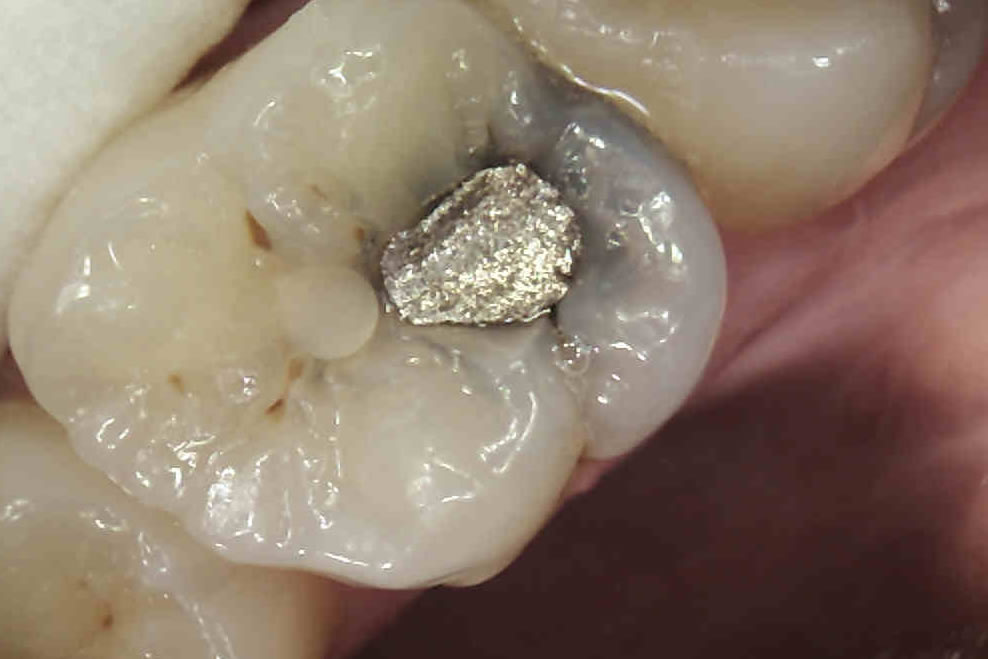

YAY! NO MORE DARK FILLINGS

WHITE FILLINGS

Composite fillings can also be used for cosmetic purposes to restore chipped or uneven front teeth. Many patients also opt to have composite fillings used to replace old, unsightly silver fillings.